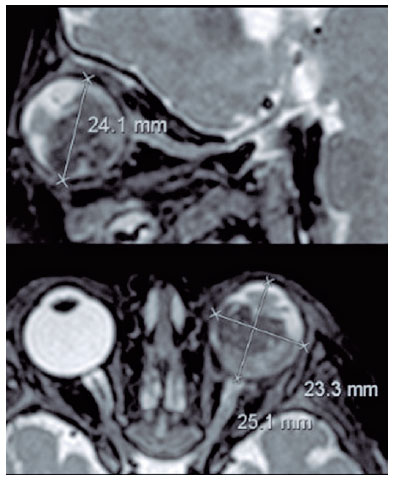

Laterality (right, left, or both eyes), growth pattern (endophytic, exophytic, or mixed), and tumor localization were analyzed. Tumor localization was identified as anterior or posterior to the equator, which is the greatest globe diameter. Moreover, posterior to the equator can be divided into macular, juxtapapillar, and none of the above. Tumor size was measured as its maximum diameter.

MRI parameters for tumor characteristics and invasion of the optic nerve, choroid, sclera, and ciliary body were examined. The maximal tumor diameter on transverse post-contrast T1 was calculated and classified as <10 mm, 10-15 mm, and >15 mm. The presence of tumor calcification was defined by dark signal spots on both T1WI and T2WI without enhancement. For quantitative analysis of diffusion-weighted MRI (DWI), the solid components of the retinoblastoma were identified on T2WI and post-contrast T1WI. Regions of interest (ROIs) were manually placed within the solid part of the tumor to avoid bias from necrotic and hemorrhagic elements, and the ADC map values of the solid components of each tumor were measured. The average ADC map values of the three measurements were used for further analysis. In bilateral tumors, the ADC map value of the enucleated eye was used for further analysis.

Diffusion coefficients were measured on the ADC map, consisting of three measurements, with ROI ranging from 0.5 to 0.3 cm, covering the largest possible area in each lesion and averaging between values.